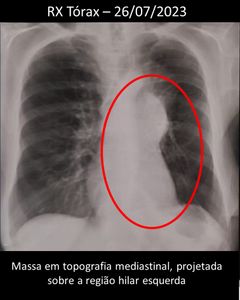

Ao mesmo tempo, dona Dulce investigava a causa do aumento de sua asma brônquica, que não se resolvia com medicamentos para asma e antibióticos. Em fevereiro, num atendimento no Pronto socorro, fez raio x do pulmão, que não apresentou alteração. Continuou-se o tratamento com medicamentos e nada ajudava. Em junho fez outro raio x, e aí sim, uma massa no pulmão apareceu. Dulce também foi encaminhada para oncologia e em agosto, internada, o diagnóstico: Carcinoma pulmonar de pequenas células, e para completar, em setembro, o diagnóstico de metástase na cabeça.